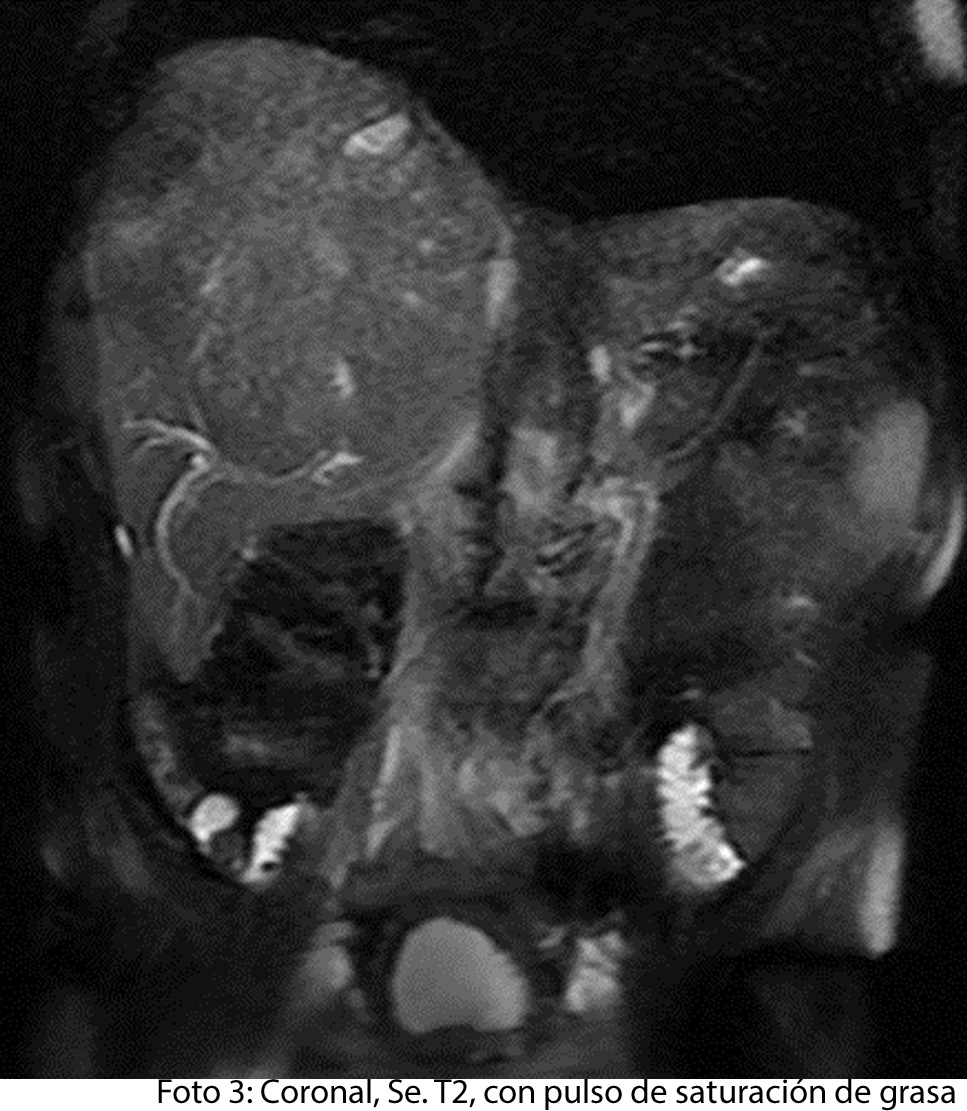

TECNICA EMPLEADA

Se procede a atender a paciente luego de cumplir con los protocolos para la realización de estudios de resonancia, paciente ingresa a zona 4, se coloca en posición decúbito supino, se utiliza gating respiratorio, estudio se obtiene con uso de bobina phase arrays, PSP Axial, sagital y coronal, secuencias Se y Gre, ponderadas a T1 y T2, se administra medio de contraste hepato especifico y se utiliza protocolo para estudio dinámico.

HALLAZGOS IMAGENOLOGICOS

• HEPATOCARCINOMA FIBROLAMINAL QUE COMPROMETE TODO EL LÓBULO DERECHO DEL HÍGADO

Es un método utilizado en el cual podemos observar una gran masa localizada en los segmentos del hígado también se puede medir el diámetro de la masa, el hepatocarcinoma también puede presentar focos hemorrágicos y además podemos captar de manera heterogénea el medio de contraste intravenoso. En los hepatocarcinomas podemos ver obstruyendo parcialmente la vena porta. Adenomegalias los cuales nos indican Los hallazgos como primera posibilidad diagnóstica, carcinoma hepatocelular fibrolamelar (CHC-FL).